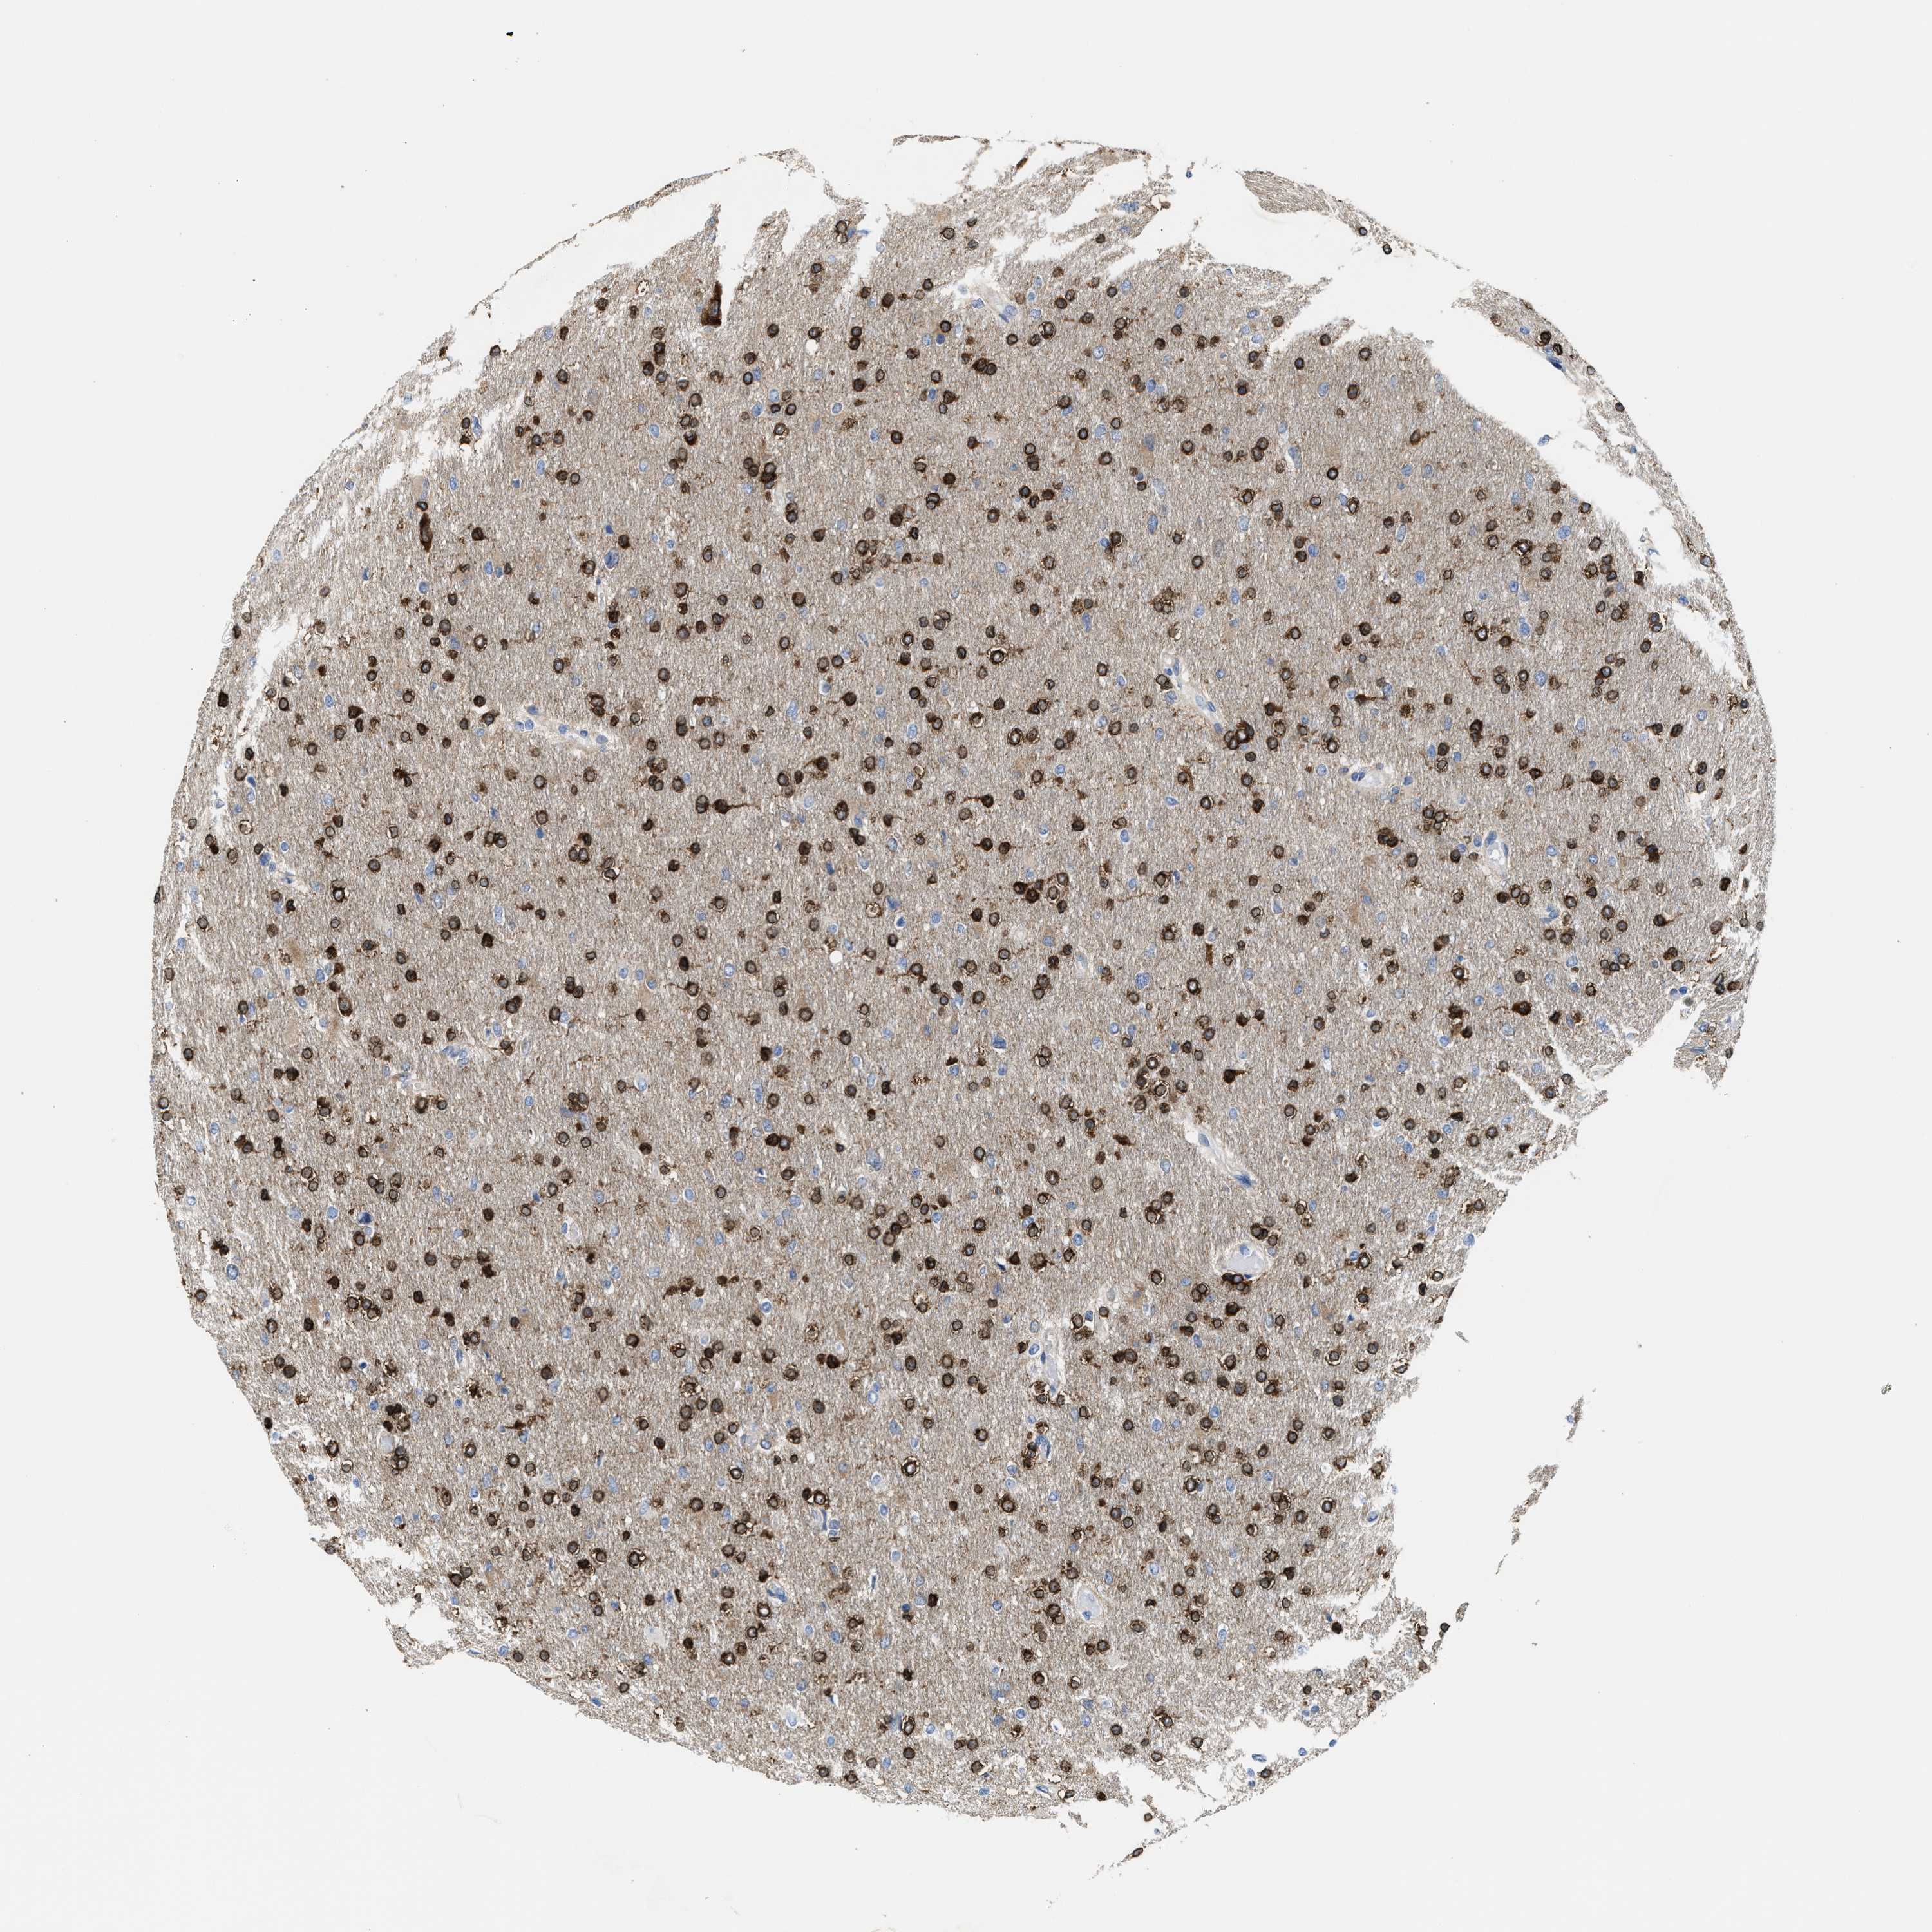

GLIOMA - Protein expressioni

A mouse-over function shows sample information and annotation data. Click on an image to view it in a full screen mode. Samples can be filtered based on level of antibody staining by selecting one or several of the following categories: high, medium, low and not detected. The assay and annotation is described here.

Note that samples used for immunohistochemistry by the Human Protein Atlas do not correspond to samples in the TCGA dataset.

Antibody stainingi

Antibody staining in the annotated cell types in the current human tissue is reported as not detected, low, medium, or high, based on conventional immunohistochemistry profiling in selected tissues. This score is based on the combination of the staining intensity and fraction of stained cells.

Each image is clickable and will lead to virtual microscopy that enables deeper exploration of all samples and also displays staining intensity scores, fraction scores and subcellular localization as well as patient and tissue information for each sample.

Antibody HPA019324

Staining

High

Medium

Low

Not detected

Intensity

Strong

Moderate

Weak

Negative

Quantity

>75%

75%-25%

<25%

None

Location

Nuclear

Cytoplasmic/membranous

Cytoplasmic/membranous,nuclear

Glioma, malignant, High grade

Glioma, malignant, Low grade